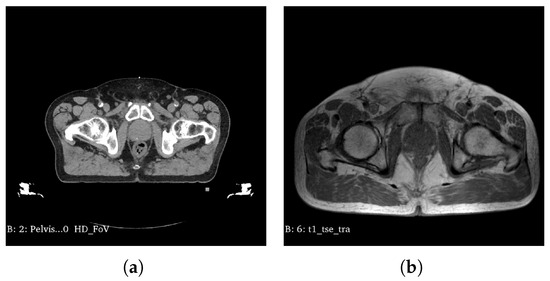

Figure 1 presents the equivalent medical image slice of CT (a) and MRI (b) for the same patient.

Sample (a) CT scan, (b) and its corresponding MR image.